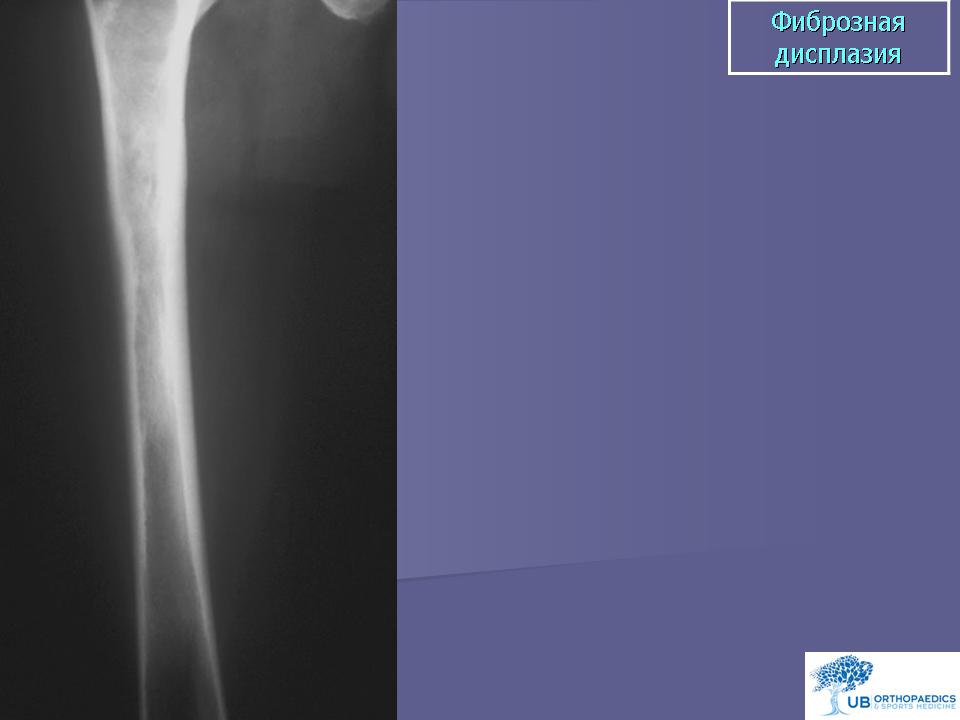

Фиброзная дисплазия. Этиология неизвестна. Заболевание наблюдается в возрасте 10-30 лет. Клинически различают монооссальную и полиоссальную фиброзную дисплазию. При некоторых формах полиоссальной дисплазии поражаются три системы - кожа (пигментация), кости и эндокринная система. Опухоль содержит низкодифференцированную доброкачественную фиброзную строму с образованием кости. Фиброзная дисплазия характеризуется медленной резорбцией костной ткани, вызывая неопределенные ноющие боли в костях, часто сочетается с патологическим переломом, причем в значительном числе случаев заболевание обнаруживается лишь после внезапно наступившего патологического перелома. При полиоссальной форме поражается несколько костей, иногда лишь на одной стороне. Заболевание необходимо дифференцировать с патологическими переломами, возникшими на фоне злокачественных опухолей костей, в частности с высокодифференцированной остеогенной саркомой (low grade). Против наличия высокодифференцированной остеогенной саркомы говорит отсутствие анаплазии и полиморфных по размерам и форме ядер в клетках фиброзной стромы. При сканировании костей могут выявляться «горячие» очаги. Рентгенологически в зонах поражения видны участки просветления («часовое стекло», «мыльные пузыри»), могут выявляться множественные патологические переломы. При сращении таких переломов проксимального конца бедренной кости в зоне поражения фиброзной дисплазией возникает симптом, называемый «пастушьим посохом (клюкой)». Пациенты с полиоссальной фиброзной дисплазией должны быть обязательно обследованы на предмет скрытых гормональных и метаболических нарушений. Малигнизация фиброзной дисплазии происходит редко (0,5%).

Фиброзная дисплазия